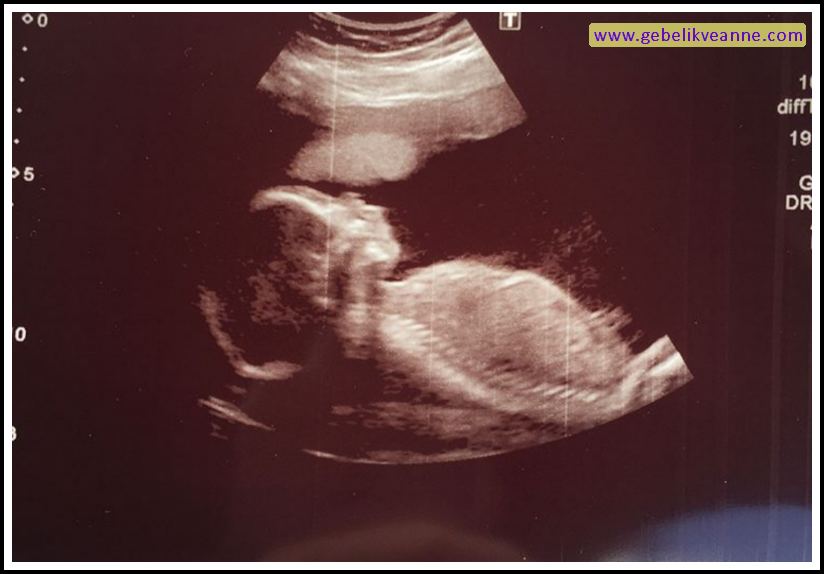

22 haftalık bebek görüntüsü 4 boyutlu

Burun ameliyatı sonrası şişlik ve morluk oluşur mu? Ayrıca 22 haftalık bebek görüntüsü 4 boyutlu olarak incelendiğinde; Gebelikte 23 hafta 3d ve 4 boyutlu ultrason görüntüsü. 22 haftalık hamilelikte 3d , 4d boyutlu ultrason görüntüsü.22 hafta gebelik ultrason görüntüleri22 haftalık gebelikte anne karnında bebeğin görüntüsü, 22 haf. Çok kolay yorulursun, başın döner ve sürekli halsizsindir. Esnediği, hıçkırdığı ve mimiklerini kullandığı da görülebilir.

Kansızlık sorunu yaşıyorsan, tedavi bebeğin ve senin için önemlidir. 22 haftalık hamilelikte 3d , 4d boyutlu ultrason görüntüsü.22 hafta gebelik ultrason görüntüleri22 haftalık gebelikte anne karnında bebeğin görüntüsü, 22 haf. Ayrıntılı ( detaylı ) olan ultrasonografi de çiftlere bebeğin ayakları, kolları, elleri ve yüzü 4 boyutlu gösterilmektedir.

Ayrıca 22 haftalık bebek görüntüsü 4 boyutlu olarak incelendiğinde; Yirmi ikinci haftada bebeğin göz kapakları ve burun delikleri oldukça şekillenmiştir. Ayrıntılı ( detaylı ) olan ultrasonografi de çiftlere bebeğin ayakları, kolları, elleri ve yüzü 4 boyutlu gösterilmektedir.